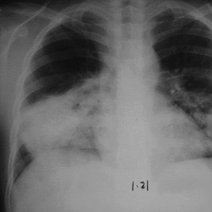

白肺的意思是指胸片、CT上发现正常肺组织透X线是黑色,只有心脏和大血管是白色,但是由于各种疾病、各种致病因素,导致两肺野呈大片的密度增高,出现白色的阴影,就...47600人收听

白肺一般是指重症肺炎在X光检查下的表现,肺部呈现一大片的白色状态而闻名。形成白肺一般都预示着肺部被炎症所广泛浸润,引起白肺的病因往往非常复杂,并且来势凶...28117人收听

白肺是指患者在X光胸片检查或者肺部CT检查中,肺部间质组织呈现大片状白色状病变的表现。白肺的症状表现多发生于重症肺炎,因为肺部间质组织持续性受到病毒、细...60057人收听

白肺(White lung)是一种临床综合症,其特征是重度肺炎患者的肺部积累了大量渗出物,影响多个肺叶,使肺部影像学检查呈现出大范围的白色区域。病因多为新型冠状病毒感染、细菌性肺炎、中东呼吸...

[最佳答案] 白肺是放射学名词,所谓白肺是指胸片或者CT上弥漫的高密度影,使得片子看不到肺纹理。导致白肺发生的原因很多,常见的大叶性肺炎、肺水肿,或者是病毒性肺炎比如SARS,以及流感、病毒引起的肺炎都会导致白肺。 至于能不能治愈要根据疾病的不同来决定, 白肺是放射学名词,所谓白肺是指胸片或者CT上弥漫的高密度影,使得片子看不到肺...